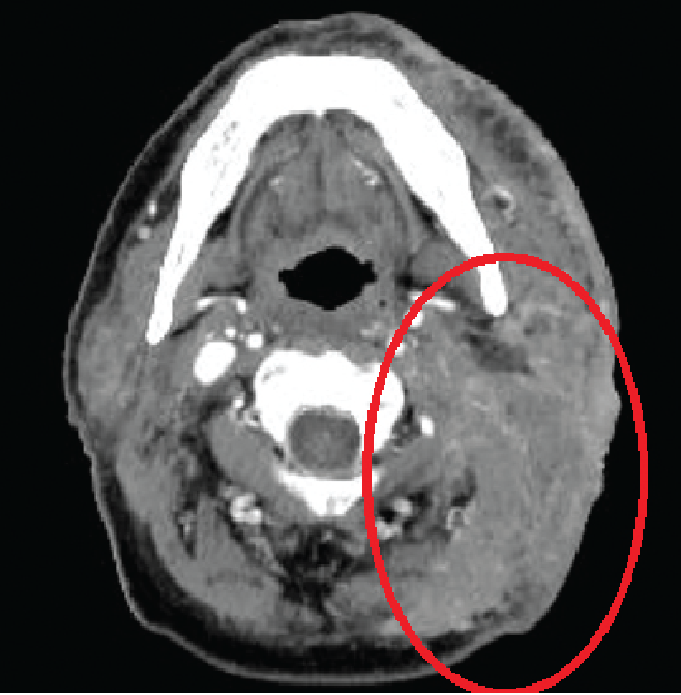

Mr. Lee

(Cameron Highlands, Chinese Malaysian)

Notes: Elderly and frail, chemotherapy not recommended. Radiotherapy prioritized.

Treatment Plan::

1. Genetic Testing: Identify potential targeted therapy options.

2. Radiotherapy: Combination of GyroKnife, Linear Accelerator, and Electron Beam

• Treatment Area: Entire left neck region

• Expected Outcome: Significant reduction in tumor size

3. Nutritional Support Therapy

Post-Treatment Outcome:

After 3 weeks, tumor size significantly reduced. Improved appetite and mobility

Before Treatment

After Treatment